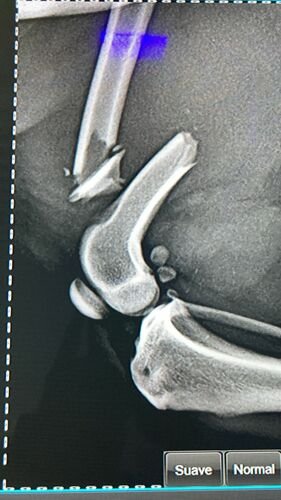

Contudo, na manhã do dia 31 de janeiro, Maya quebrou o fêmur da perna traseira esquerda. Para realizar a cirurgia, precisamos de R$3.500,00. Conseguimos negociar os outros gastos, como a consulta inicial, mas a cirurgia é muito mais crítica.